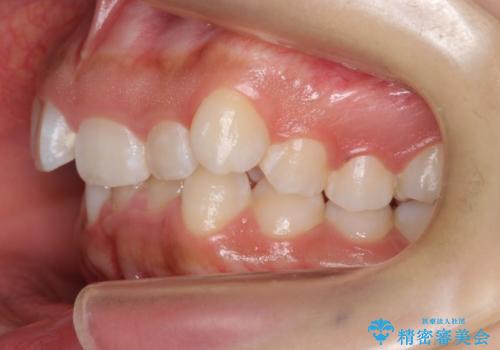

前歯のがたがた 前歯が内側に傾いている

- 前歯のがたがたを主訴に来院。

上の歯並びが前にずれて、さらに前歯が内側に倒れて過蓋咬合を呈していました。